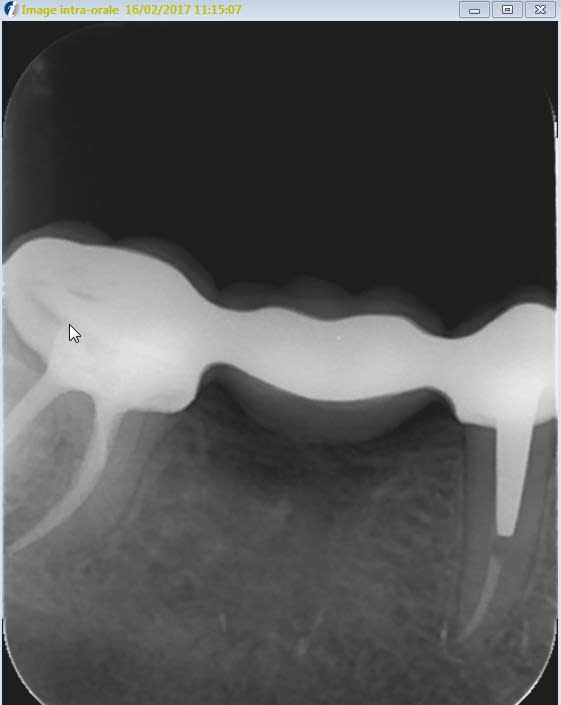

Bon j'ai repris une radio de la 47,une fois le bridge posé, pour contrôler l'adaptation et en même temps vérifier que je ne suis pas à 2 mm du dôme apicale radiologique.

D'après la mesure effectuée sur le logiciel cliniview, je suis à seulement à 0.6 mm de l'apex radiologique.